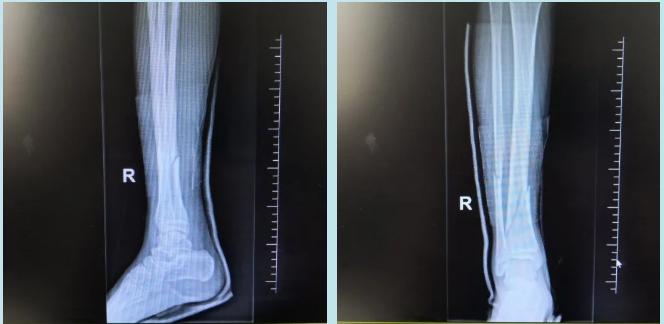

小佟是金平区一所中学的初三学生,刚开学的第二天,小佟在学校踢足球时摔伤,出现了右小腿肿痛伴活动受限,伤后送至医院查X线片显示“右胫腓骨骨折”,医师即予手法整复并右下肢高分子夹板外固定。经处理后病情稳定,骨折处对位对线良好。